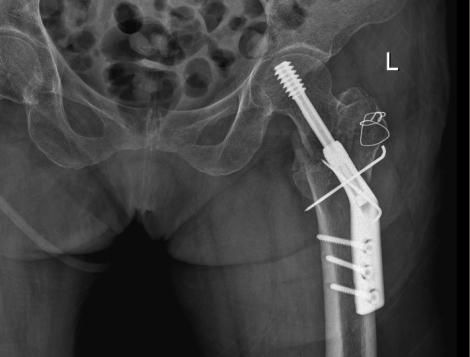

△骨科于15日、16日收治的另外兩位高齡患者

△術前

△術後